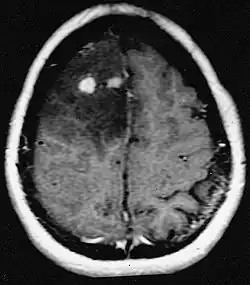

Primair lymfoom van het centrale zenuwstelsel is goed voor ongeveer 2 procent naar 3 procent van alle hersentumoren bij patiënten met een normaal immuunsysteem. Ze komen vaker voor bij mannen boven de 55 tot 60 jaar op. Bijna de helft van alle lymfomen komt voor bij patiënten ouder dan 60 jaar en ongeveer een kwart bij patiënten ouder dan 70 jaar jaar op. De incidentie lijkt toe te nemen met de leeftijd, maar de reden is nog steeds onduidelijk. Patiënten met een verzwakt immuunsysteem lopen een groter risico op het ontwikkelen van CZS-lymfoom, dus degenen die een orgaantransplantatie hebben ondergaan, hebben een aangeboren immunodeficiëntie of auto-immuunziekte, of zijn geïnfecteerd met het humaan immunodeficiëntievirus. HIV-geassocieerde hersenlymfomen zijn geassocieerd met het Epstein-Barr-virus, vooral bij patiënten met CD4-lymfocytentellingen van minder dan 500 cellen per kubieke millimeter in het bloed. De meeste CZS-lymfomen zijn grote B-cellymfomen van het type.

Patiënten lijden aan een verscheidenheid aan karakteristieke symptomen van een focale of multifocale massieve laesie. MRI toont meestal tumoren met homogene contrastversterking in de diepe periventriculaire witte stof. Multifocaliteit en inhomogene versterking zijn typisch voor patiënten met een verzwakt immuunsysteem. Analyse van CZS-lymfoom is uiterst belangrijk bij de differentiële diagnose van hersenneoplasie. Opgemerkt moet worden dat de toediening van corticosteroïden kan leiden tot het volledig verdwijnen van de versterking, waardoor de diagnose van de laesies moeilijk wordt. Als daarom CZS-lymfoom moet worden overwogen bij de differentiële diagnose, moeten corticosteroïden worden vermeden, tenzij het massa-effect een ernstig en onmiddellijk probleem bij de patiënt veroorzaakt.

Biopsie van de vermoedelijke laesie is cruciaal. In tegenstelling tot systemisch grootcellig B-cellymfoom, waarbij zowel chemotherapie als radiotherapie effectief zijn en de behandeling van gelokaliseerde laesies curatief is, reageert lymfoom van het centrale zenuwstelsel doorgaans op initiële therapie, maar keert daarna terug. Net als bij systemisch lymfoom is de rol van chirurgie voornamelijk beperkt tot het verkrijgen van geschikte weefselmonsters voor diagnose.